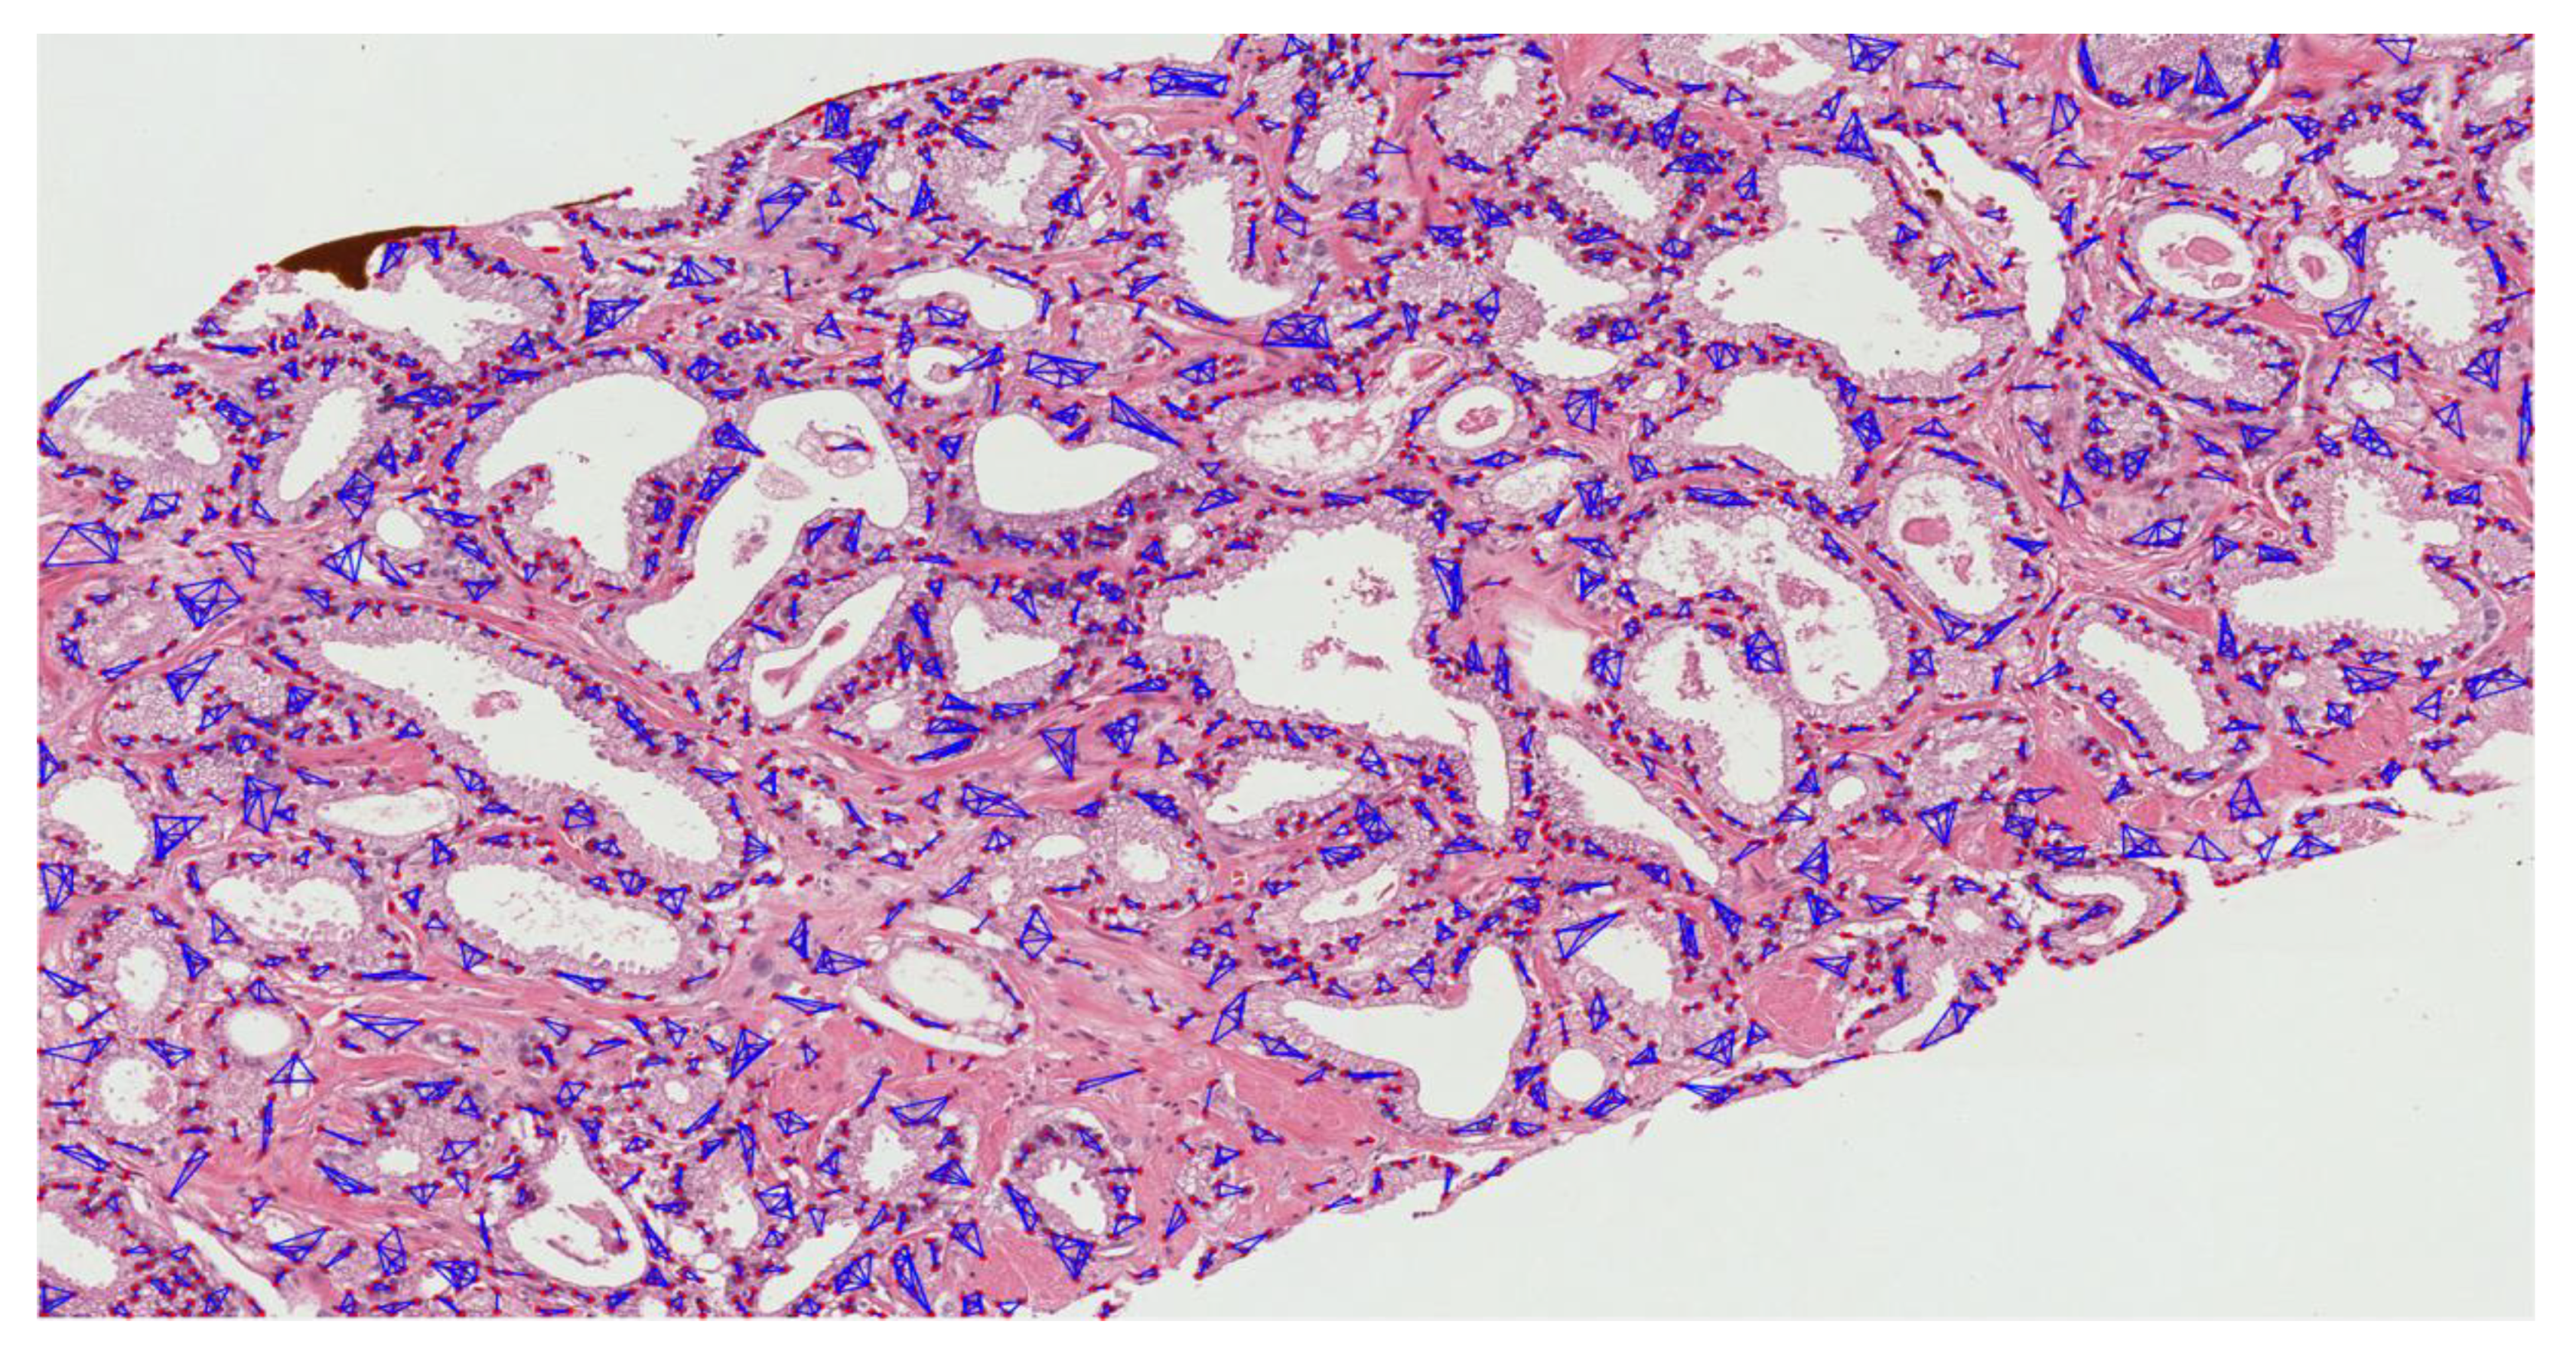

3.2.2. Nuclear Segmentation of Cancer Cells

3.2.3. Cluster Analysis